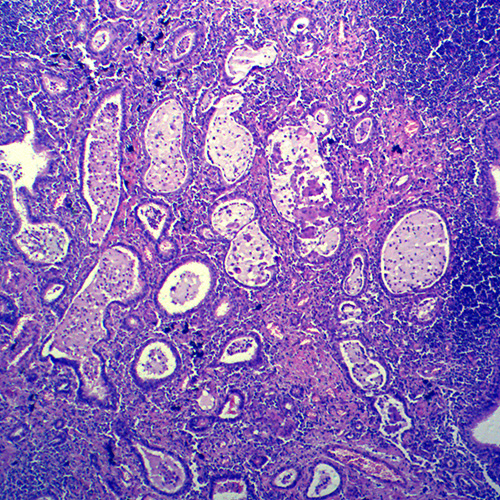

湖南炎症病理玻片

产品内容说明 /Product description

人体病理切片,炎症病理玻片,炎症病理玻片价格